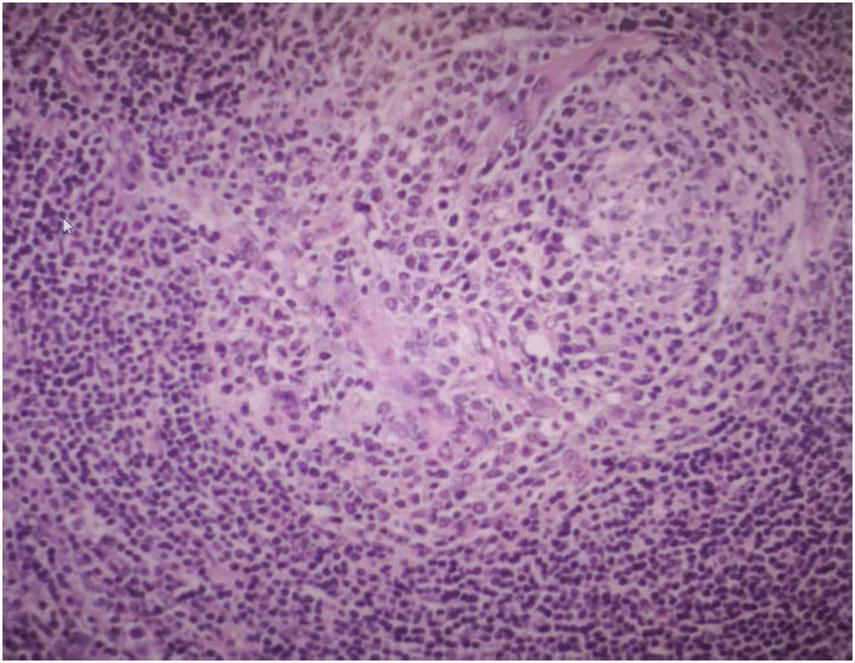

Three days after being admitted to hospital, the patient subsequently underwent surgery to completely resect the retroperitoneal mass under general anesthesia. A large mass, approximately 10 cm × 6 cm in size, was detected in the left retroperitoneum. It was well-defined and showed no infiltration into surrounding tissues, allowing for complete excision. Postoperative pathological examination confirmed the diagnosis of UCD, hyaline-vascular type (Figure 3). Immunohistochemical staining results were as follows:CD20 (lymphoid follicle cells +), CD79a (lymphoid follicle cells +), CD3 (interfollicular area cells +), CD5 (interfollicular area cells +), CD21 (follicular dendritic network +), Bcl-2 (follicular dendritic network and surrounding lymphocytes +), CD10 (focal +), CD138 (focal +), Cyclin D1 (scattered +), CD30 (individual cells +), Ki-67 (+).

FIGURE 3

Postoperative pathological examination showed the mass is UCD, hyaline-vascular type.